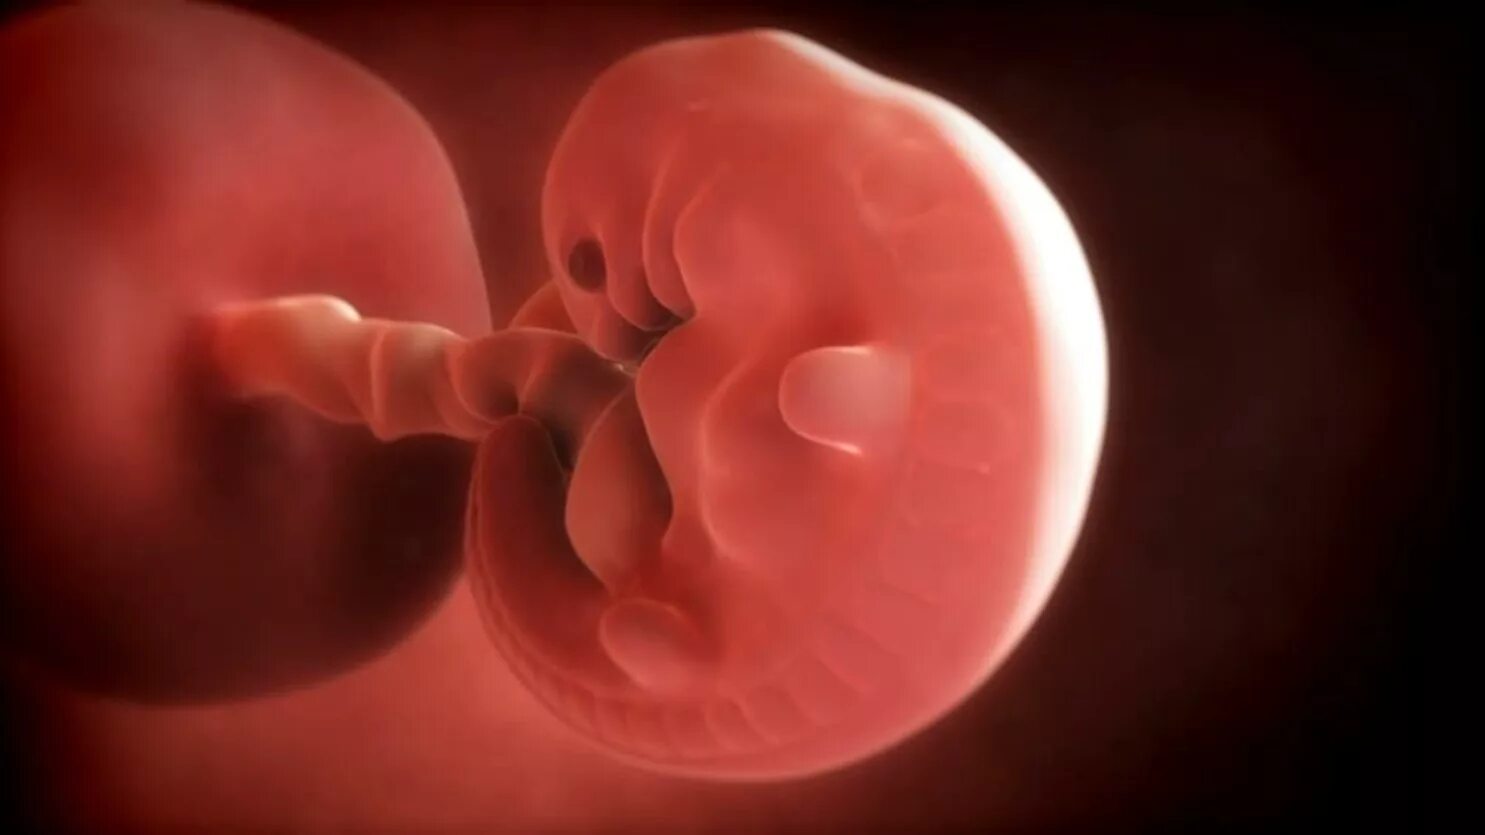

Эмбрион не прикрепился к матке причины